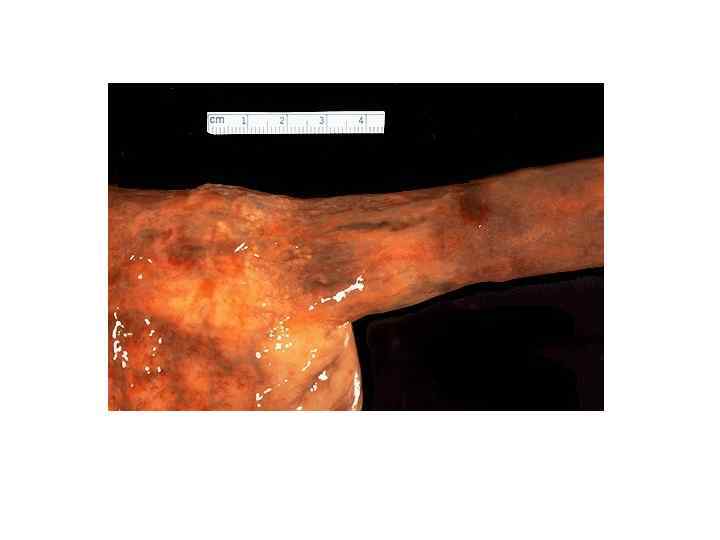

Цирроз печени • -диффузный процесс, который характеризуется избыточным развитием фиброзной ткани и образованием регенераторных узлов с нарушением архитектоники печени и развитием внутрипеченочных сосудистых анастомозов. • МАКРОскопически выделяют: • -микронодулярный (узлы 1 -3 мм) • -макронодулярный (более 3 мм) • -смешанный

Злокачественные опухоли печени • МАКРО- три формы -узловая -диффузная -массивная Ткань серого цвета, зеленовато-серого цвета, плотной консистенции с очагами кровоизлияний и зонами распада